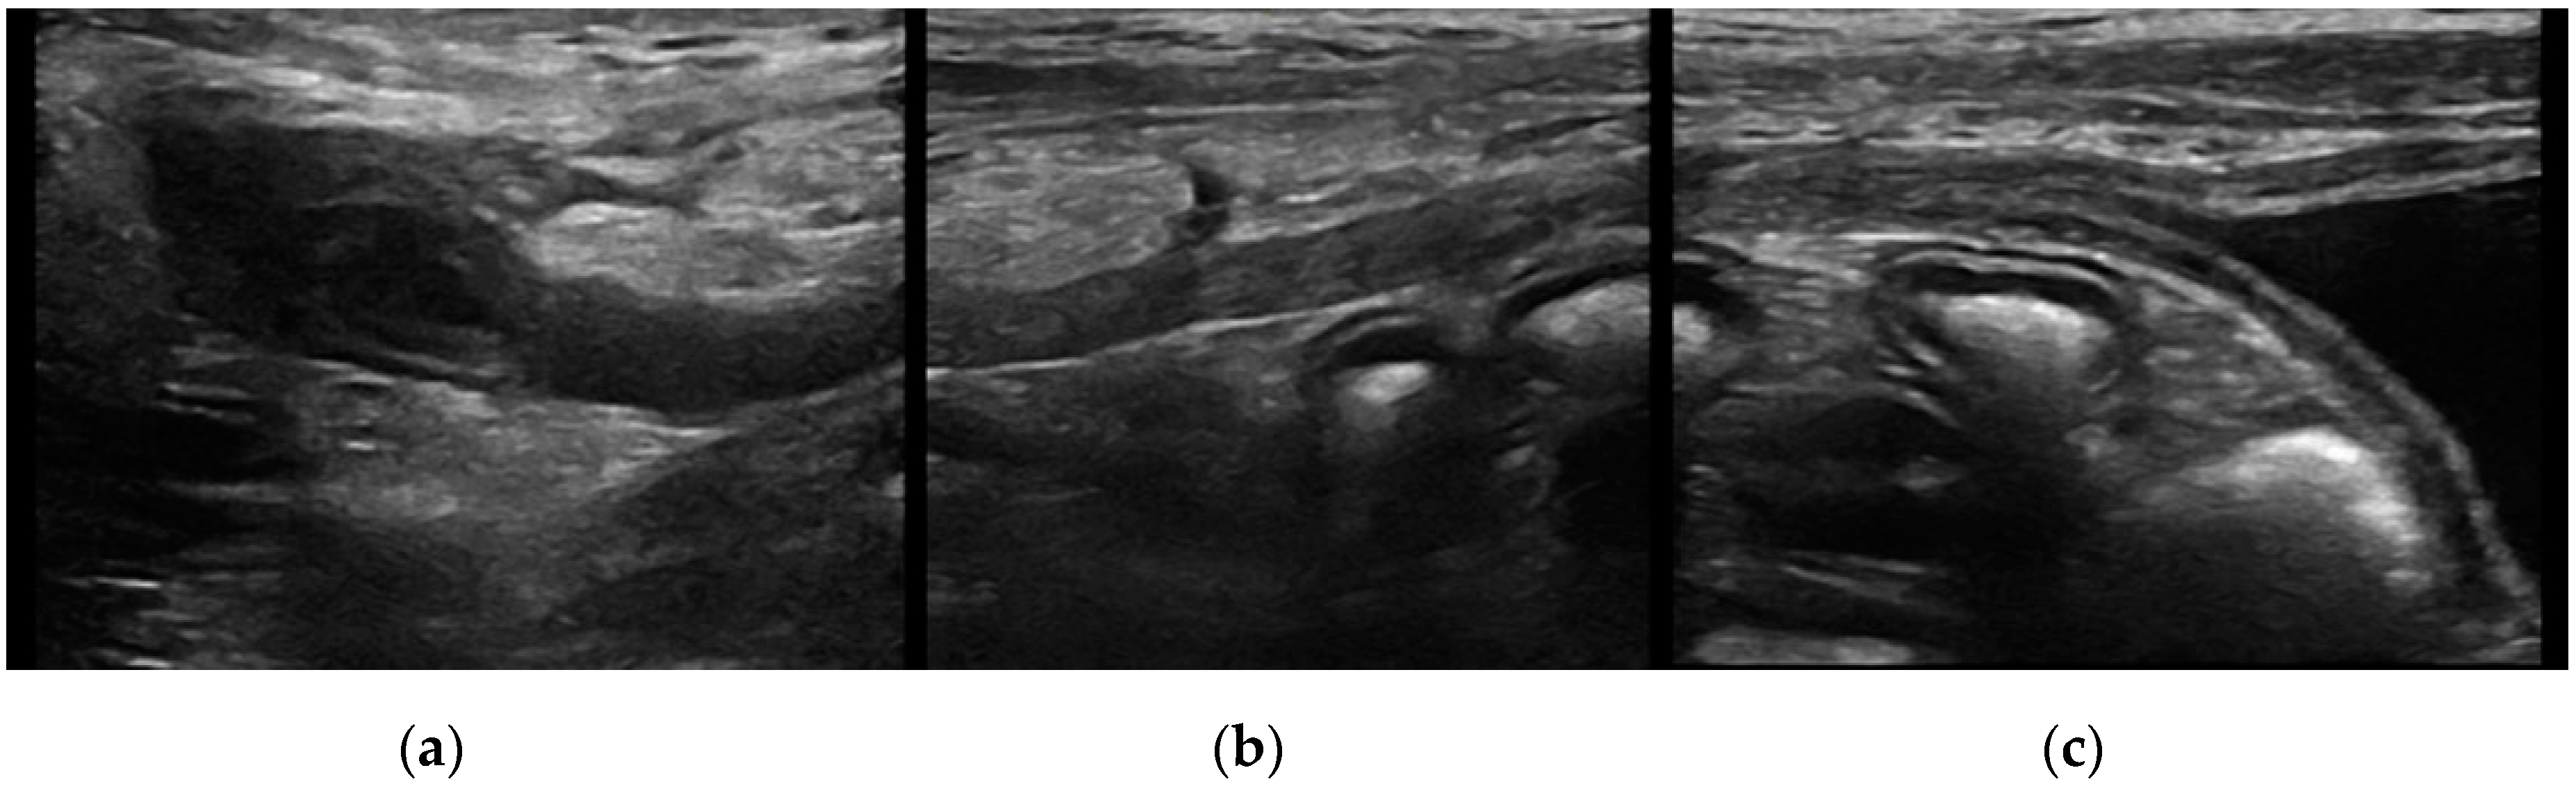

Intramural vesicourachal diverticulum was the most prevalent UA diagnosed in both cats (76.7%), and dogs (71.1%). These varied in size, from thin anechogenic lines perpendicular to the wall, in the ventro-cranial portion of the bladder, to formations of greater width, up to 0.4–0.5 cm. Its content was variable, from anechoic to slightly corpuscular, in relation to the bladder corpuscularity (Figure 2).

Figure 2. Longitudinal ultrasound image of the urinary bladder in a dog, showing the presence of a small (<1 cm diameter), well-defined, fluid-filled, anechoic structure in the cranioventral bladder wall, consistent with intramural vesicourachal diverticulum.